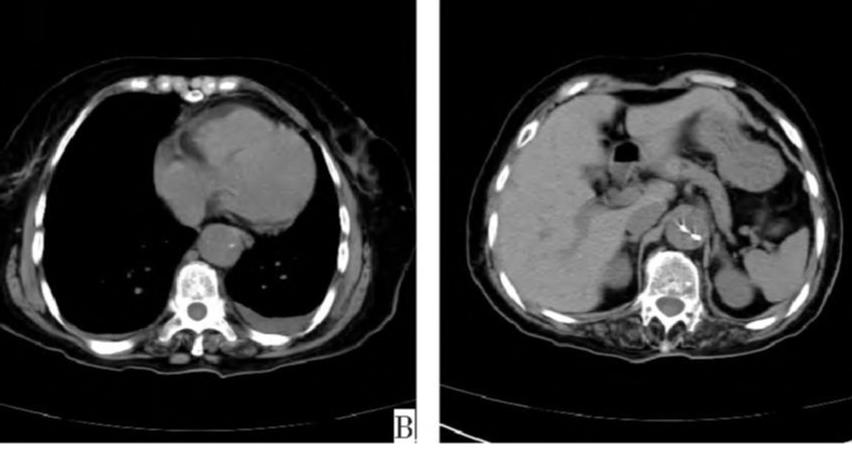

病例6

有些小伙伴开始着急了: 鲁迅你别说了,我们家的CT分辨率低,平扫绝对看不出动脉夹层!

下图的胸部CT平扫,有什么致命的问题?

图15

血管壁钙化啊,老年人很常见啊,能说明个锤子!

注意,看下面,钙化在血管的里面,不是在管壁!难道是血液钙化了?血液钙化?什么鬼?

图16

这不是血液钙化,这是主动脉夹层导致的血管钙化内移!血液不会钙化,因为动脉夹层,导致钙化的内膜被压迫进入血管!

增强CT一看,就一清二楚了!

图17